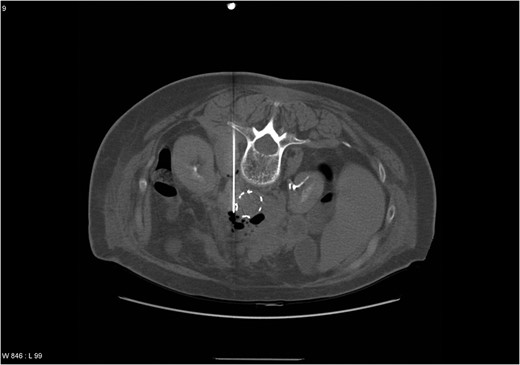

Three months postoperatively, she was admitted with sepsis and pain in her right foot. Computer tomography (CT) confirmed a plantar abscess which was treated surgically. Intravenous Ciprofloxacin and Cloxacillin were administered for 10 days followed by oral antibiotics for 1 week. Supplementary CT angiography (CTA) was performed, revealing a 4.2 cm large pseudoaneurysm at the cranial graft anastomosis. Microbiological cultures grew negative. The patient responded following 3 weeks of intravenous Cloxacillin. The pseudoaneurysm was followed with ultrasound every 6 months until a diameter of 5.2 cm in December 2004. To exclude the pseudoaneurysm, a stentgraft (Endurant®, Medtronic) was implanted in March 2005. Early onset postoperative sepsis complicated the course, and CTA revealed abscess formation in the pseudoaneurysm. CT-guided puncture was performed (Fig. 1). Cultures grew Streptococcus milleri, Eikenella corrodens and Bacterioides sp. Meropenem was administered with clinical response. Four weeks after stentgraft implantation, open revision of infected and necrotic tissue was performed. The graft implanted in 2003 and the stentgraft were partially exposed in a range from 2 to 5 cm distal from the renal arteries. A fistula from the last part of duodenum to the aneurysm sac was closed surgically. A decision was made not to explant the grafts due to impaired general condition and high age, and that graft excision would include suprarenal aortic clamping. Gentamycin (Gentacoll®) sponge was applied locally on the grafts and coverage with omentum was performed. Two weeks postoperatively, the patient was discharged with Ciprofloxacin and Clindamycin for 3 months. In June 2005, CTA revealed no sign of infection and antibiotics were continued for 6 months. In 2007, she presented with fever, and blood cultures grew Actinomyces. A decision was made to treat with antibiotics indefinitely. During the period 2008–13, the patient was admitted at several occasions with sepsis, successfully treated.

CT scan showing an abscess formation around the aortic stentgraft and a needle in the abscess for drainage. Note the presence of air bubbles in the abscess.